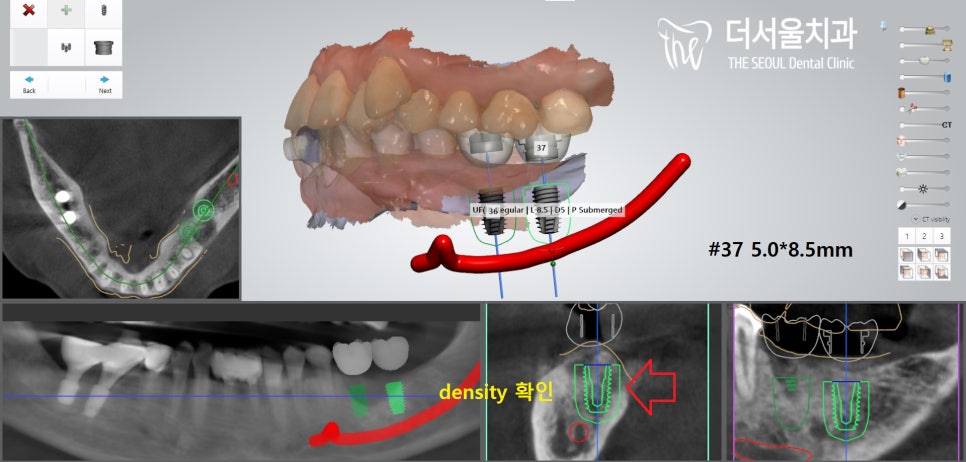

3. 디지털 임플란트

태평역치과 에서는

이를 뽑은 자리에

디지털 임플란트를 계획했습니다.

상실된 어금니의 역할을

대신하기 위한 것으로

이렇게 구강 스캔 데이터와

CT를 분석하여

디지털 임플란트의 식립 위치와 방향을

결정할 수 있습니다.

아래턱 내부에는 하치조 신경이라는

중요한 해부학 구조가 존재하기에

이곳과 적절한 간격을 가질 수 있도록

계획하였으며

나아가 잇몸뼈의 컨디션이

조금이라도 양호한 곳을 선택했습니다.

그래야 초기고정력을 잘 받을 수 있기 때문이죠.

이것은 디지털 임플란트의

큰 장점 중 하나랍니다.